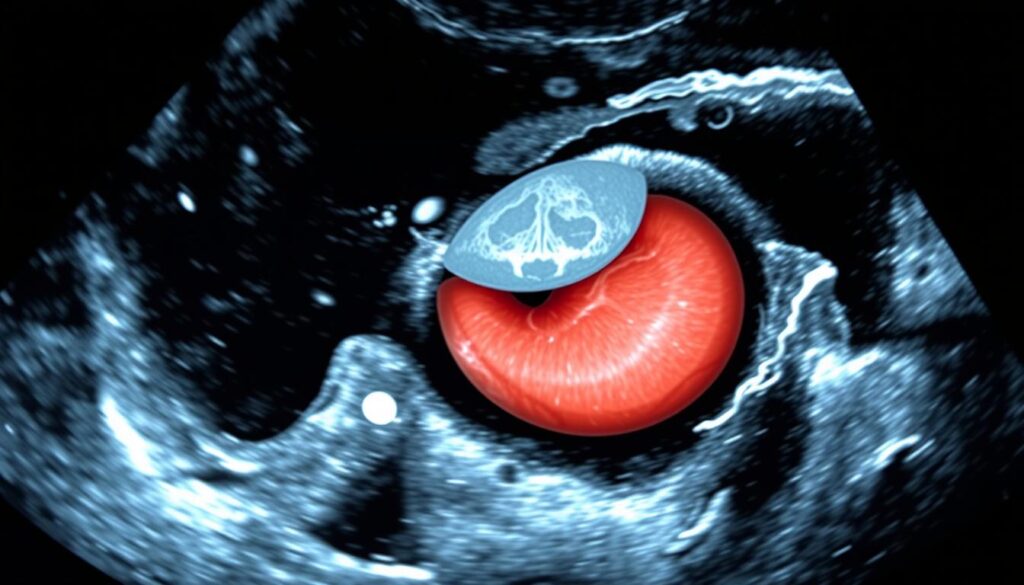

Step 5: Analyzing Aortic Morphology and Associated Pathology

The fifth step in our OCT-5595-AAA ultrasound protocol is to analyze the aortic morphology and any associated pathology. This step is key to understanding the aneurysm’s complexity and planning the right management.

Identifying Intral and Thrombus and Wall Calcification

Intraluminal thrombus and wall calcification are important factors. They can affect the risk of rupture and the management plan. Intraluminal thrombus is blood clots inside the aneurysm sac, seen as hypoechoic or heterogeneous material on ultrasound. Wall calcification is hardened plaque on the aortic wall, seen as bright echoes with acoustic shadowing.

Assessing Aneurysm Shape, Extension, and Branch Involvement

Understanding the aneurysm’s shape, extension, and branch involvement is vital. It helps in planning surgery and assessing risks. The shape, whether fusiform or saccular, affects the risk of rupture.